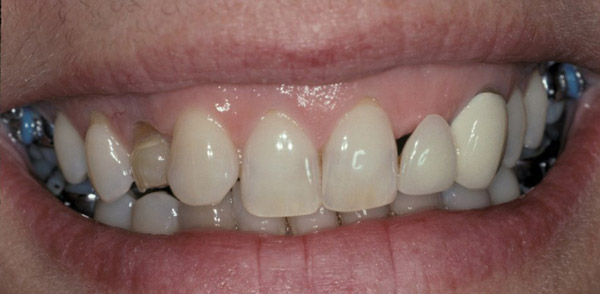

Figure 13  Initial view of this patient depicts the esthetic disharmony and smile imbalance. There was a retained primary maxillary canine on the right, a permanent canine in place of the right lateral incisor, a missing tooth No. 10 replaced with a cantilever restoration, asymmetric gingival margins, recession on tooth No. 11, and uneven incisal edges.

Figure 13